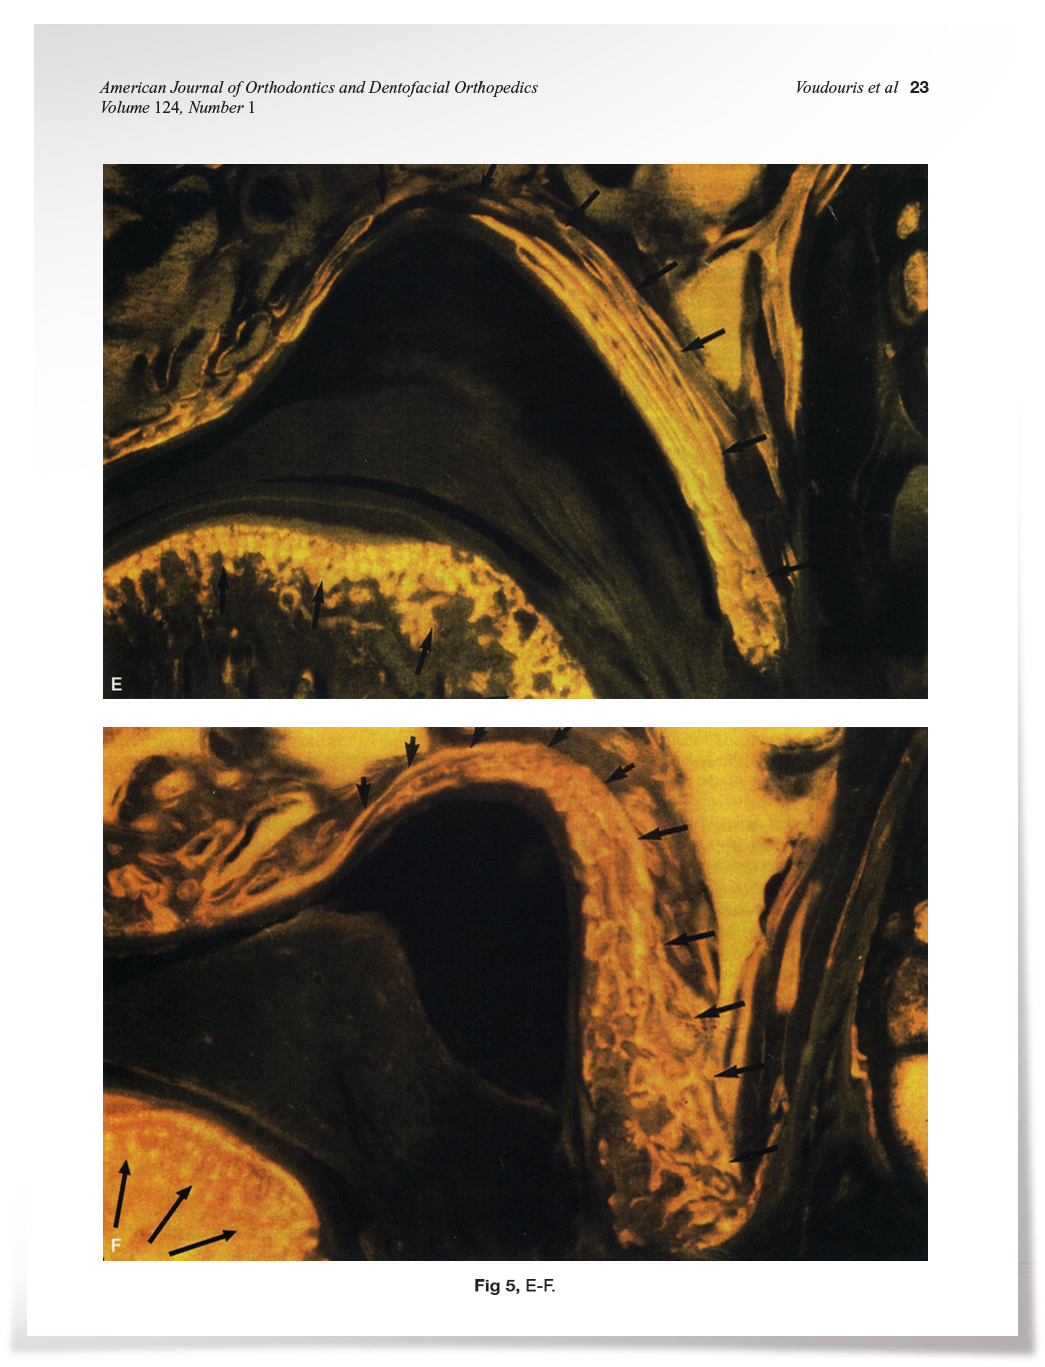

Condyle-fossa Histological Results